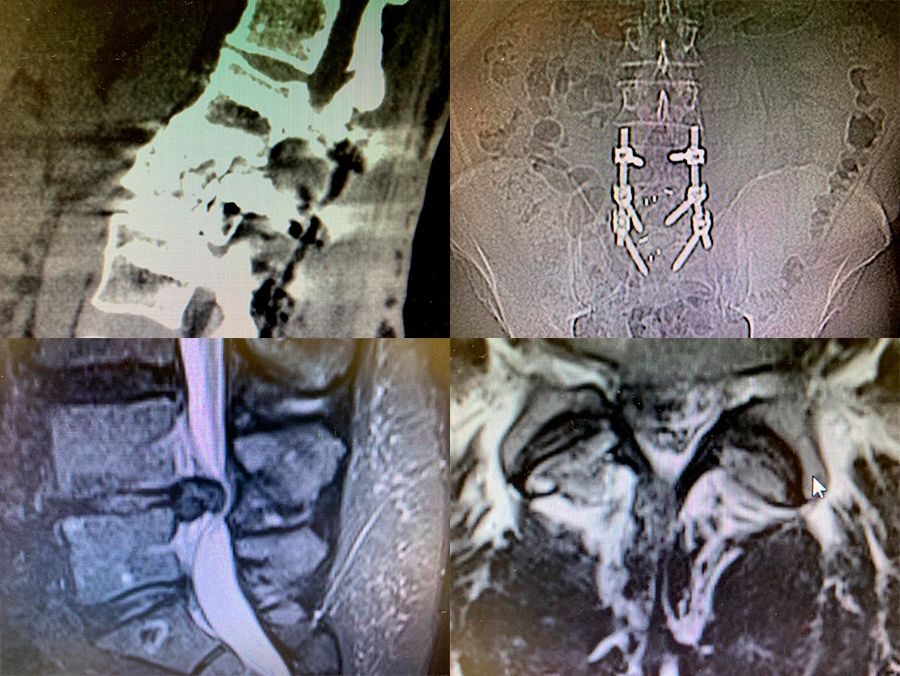

Как врач, постоянно консультирующий, встречаюсь в своей практике с уникальными медицинскими случаями, которые требуют особого внимания, сбора информации, изучения специализированной литературы, совета опытных коллег, и зачастую, мозгового штурма. Иногда, по результатам диагностики, пациент имеет абсолютные показания к сложной операции, но в 50-60 процентах случаев, после углубленного исследования, я могу предложить такую программу реабилитации, в результате которой операции удается избежать. Если получается решить задачу - помочь пациенту - испытываю радость и удовлетворение первооткрывателя! Анализ и обобщение таких случаев помогают составлять более эффективные программы реабилитации для других пациентов, использовать полученные данные в обучении специалистов